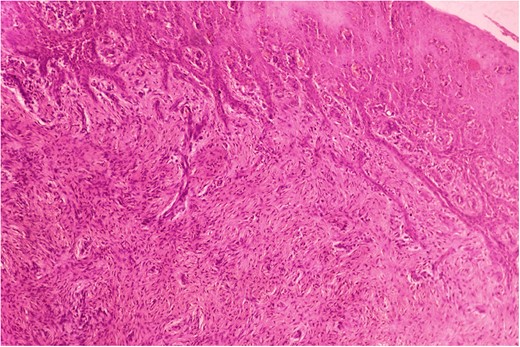

Biopsy was taken from hypertrophied and ulcerated lesion. On microscopy, tissue was lined by keratinized stratified squamous epithelium with surface ulceration. Underlying stroma showed infiltrating squamous cell carcinoma (SCC) along with extensive collagenous fibrosis (Fig. 2). Dense acute and chronic inflammations were also noted. A diagnosis of SCC with familial gingival fibromatosis was given (Fig. 3).

Histopathological picture showing islands of squamous cell carcinoma infiltrating into the stroma. (H&E, ×400).